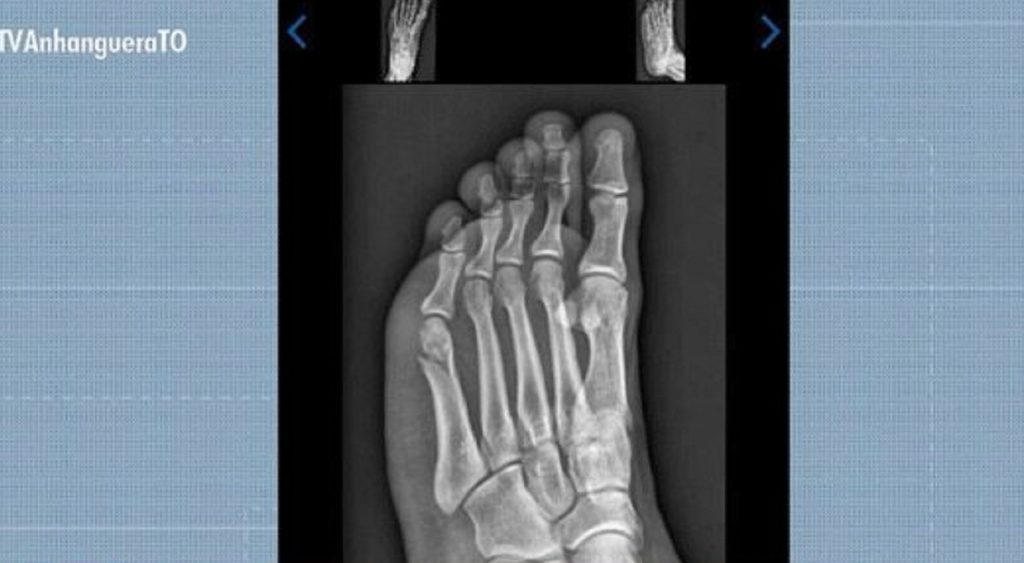

Candidato faz teste físico da PM com fratura no pé e consegue aprovação: ‘Pensei que não ia conseguir’

Candidato quebra pé dias antes do TAF da Polícia Militar

Um jovem concurseiro de Gurupi, no sul do Tocantins, conseguiu ser aprovado no Teste de Aptidão Física (TAF) da Polícia Militar mesmo com o pé quebrado. A prova aconteceu 30 dias após Gabriel Santos Rodrigues, de 22 anos, cair do telhado da própria casa enquanto trocava a boia da caixa d’água.

Mesmo em dúvida se conseguiria completar a prova, Gabriel continuou, afinal já havia passado pelas outras etapas do TAF. Ele concluiu a prova faltando três segundos para o limite.

Gabriel Santos Rodrigues foi aprovado no TAF da PMTO mesmo com fratura no pé

Reprodução/TV Anhanguera

Concurseiro concluiu prova de corrida do TAF com fratura no pé